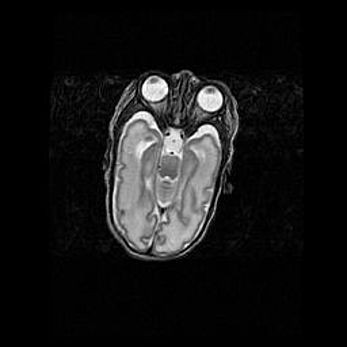

Аномалия Денди-Уокера. Признаки гипоплазии мозолистого тела.

Возраст: 5 месяцев 3 дня

Вес: 5550 г

Пол: мужской

Окружность головы: 39 см

Срок гестации: 40 недель

Аномалия Денди-Уокера – это порок развития головного мозга, для которого характерна триада симптомов: гипотрофия или аплазия червя мозжечка и/или полушарий мозжечка, расширение четвёртого желудочка с формированием ликворной кисты задней черепной ямки, гипертензионная гидроцефалия различной степени.

Гипоплазия мозолистого тела относится к дефектам внутриутробного этапа развития мозговой ткани, возникающим в процессе закладки структур головного мозга, что происходит на начальных этапах развития эмбриона.